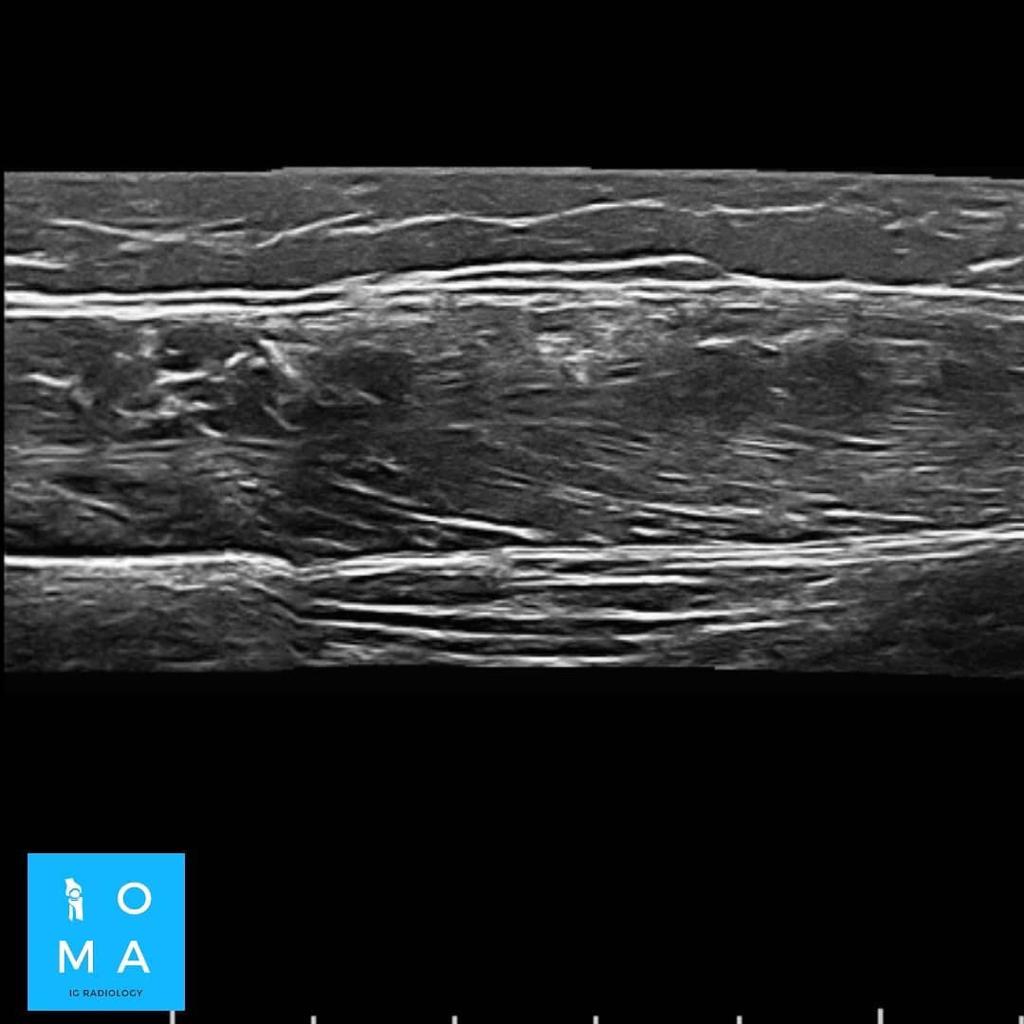

🔹En un segundo tiempo se realiza ecografía dirigida, confirmando los hallazgos a nivel del tendón central del músculo recto

anterior del cuádriceps derecho, presentando desgarro grado II, asociado a un

aumento del flujo vascular al examen Power doppler.